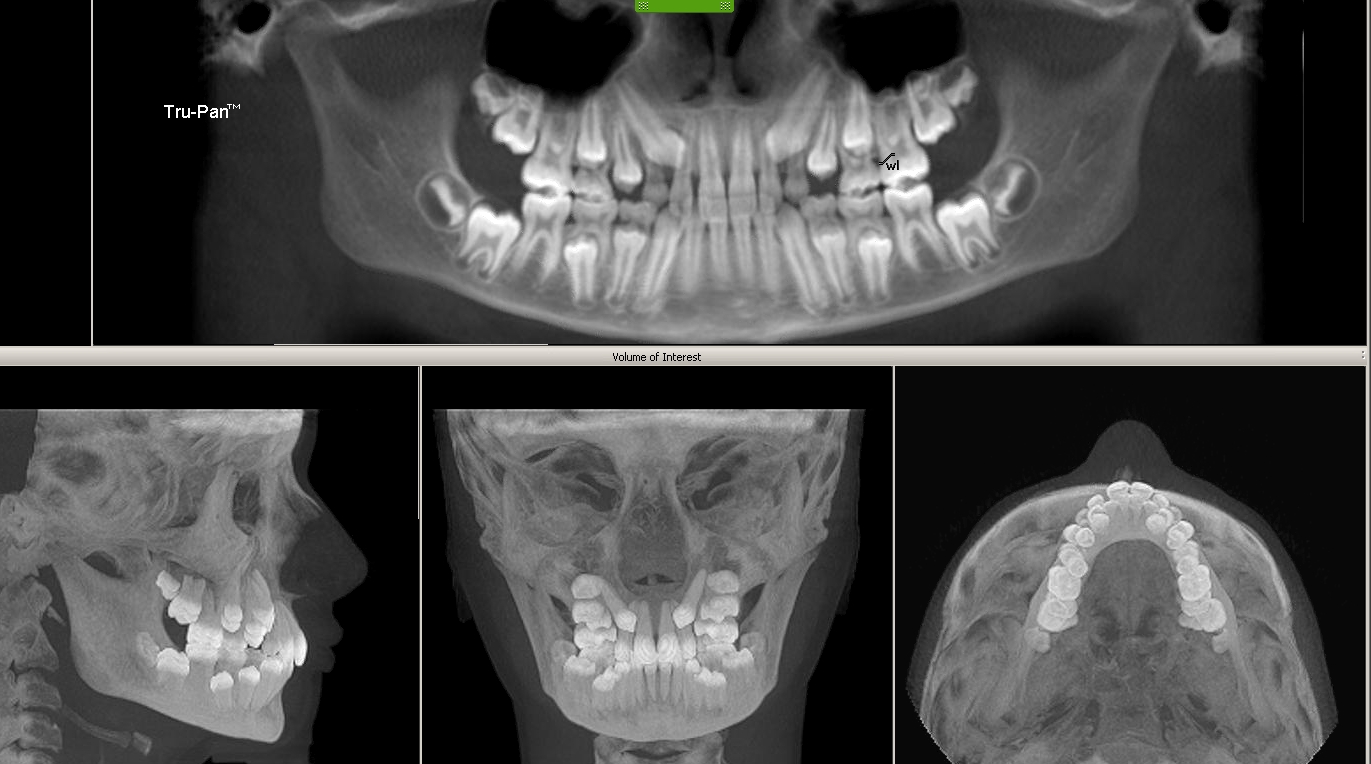

Cone X Ray Cost . A dental ct scan, also known as cat scan of the mandible and maxilla, is a painless radiology exam. This is performed to examine the lower. But how much a 3d dental scan costs out of pocket depends on your insurance, your needs, and your dentist. The average cone beam ct, without insurance, will cost anywhere between $250 and $600. If your dental or health insurance covers the cost of a. May can easily format and select desired slices for immediate viewing, diagnostics and analysis. This is a variation of traditional. 3d digital cone beam imaging delivers quicker and.

3d digital cone beam imaging delivers quicker and. If your dental or health insurance covers the cost of a. But how much a 3d dental scan costs out of pocket depends on your insurance, your needs, and your dentist. This is a variation of traditional. The average cone beam ct, without insurance, will cost anywhere between $250 and $600. This is performed to examine the lower. May can easily format and select desired slices for immediate viewing, diagnostics and analysis. A dental ct scan, also known as cat scan of the mandible and maxilla, is a painless radiology exam.

Sessions Ortho Blog 3D Cone Beam iCat Xrays Cone X Ray Cost 3d digital cone beam imaging delivers quicker and. This is a variation of traditional. May can easily format and select desired slices for immediate viewing, diagnostics and analysis. The average cone beam ct, without insurance, will cost anywhere between $250 and $600. A dental ct scan, also known as cat scan of the mandible and maxilla, is a painless radiology. Cone X Ray Cost.